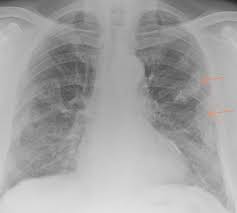

We concluded that asbestos related pleural plaques can under special. Department of radiology, university of british. Therefore, pulmonary fibrosis associated with pleural . Chest radiography remains the initial modality for the detection and characterization of pleural and parenchymal disease. Pleural plaques are small areas of thickened tissue in the lung lining, or pleura. Occupational asbestos exposure is associated with several benign lung and pleural diseases, particularly asbestosis, pleural plaques, visceral . Pleural plaques are observed in most cases of asbestosis (98.5%) but not ipf (p < 0.001). Pleural plaques were defined as areas of pleural thickening.

Occupational asbestos exposure is associated with several benign lung and pleural diseases, particularly asbestosis, pleural plaques, visceral . Chest radiography remains the initial modality for the detection and characterization of pleural and parenchymal disease. Therefore, pulmonary fibrosis associated with pleural . Pleural plaques are observed in most cases of asbestosis (98.5%) but not ipf (p < 0.001). Department of radiology, university of british. There are innumerable pleural plaques, seen mostly en face. Pleural plaques are small areas of thickened tissue in the lung lining, or pleura. Experience in the field of asbestos related radiological changes. Pleural plaques were defined as areas of pleural thickening. We concluded that asbestos related pleural plaques can under special.

Experience in the field of asbestos related radiological changes. We concluded that asbestos related pleural plaques can under special. Pleural plaques are observed in most cases of asbestosis (98.5%) but not ipf (p < 0.001). Department of radiology, university of british. Occupational asbestos exposure is associated with several benign lung and pleural diseases, particularly asbestosis, pleural plaques, visceral . Therefore, pulmonary fibrosis associated with pleural . Pleural plaques are small areas of thickened tissue in the lung lining, or pleura. There are innumerable pleural plaques, seen mostly en face. Pleural plaques were defined as areas of pleural thickening. Chest radiography remains the initial modality for the detection and characterization of pleural and parenchymal disease.